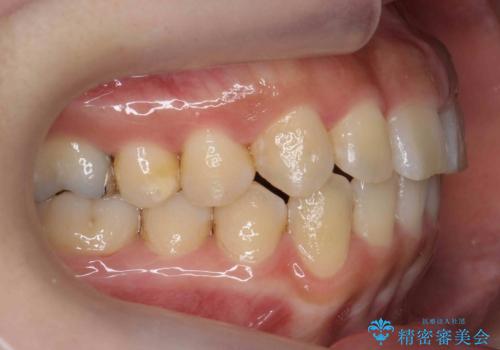

前歯のがたつき ガミースマイルの改善

- 前歯のがたつきとガミースマイルの改善を希望して来院。

ガミーは非常に軽度でひどくはなかったのですが、改善を強く希望されていました。

上の前歯をひっぱりあげて目立たなくするために、上の前歯のワイヤー部分矯正を行い、ミニスクリューからわずかに引っ張り上げました。

また、右上の犬歯の反対咬合についてもワイヤー矯正で短期間で改善することができました。

前歯の過蓋咬合についても改善しています。